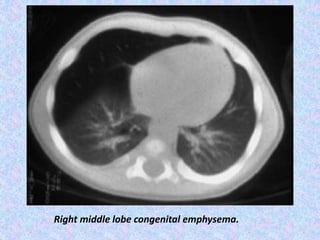

Congenital Lobar Emphysema.

CLE almost always involves one lobe, with rates of

occurrence as follows:

Left upper lobe - 41%

Right middle lobe - 34%

Right upper lobe - 21%

Congenital lobar emphysema has 2 forms:

Hypoalveolar (fewer than expected number of alveoli)

Polyalveolar (greater than expected number of alveoli)

X-Ray shows unilateral –translucency.

CT Scan shows hyperinflation of one or more lobes with

attenuated pulmonary vasculatures, compression

atelectasis of the adjacent lung and mediastinal shift.

Right middle lobe congenital emphysema.

Congenital Lobar Emphysema. CLEalmost always involves one lobe, with rates of occurrence as follows: Left upper lobe - 41% Right middle lobe - 34% Right upper lobe - 21% Congenital lobar emphysema has 2 forms: Hypoalveolar (fewer than expected number of alveoli) Polyalveolar (greater than expected number of alveoli) X-Ray shows unilateral –translucency. CT Scan shows hyperinflation of one or more lobes with attenuated pulmonary vasculatures, compression atelectasis of the adjacent lung and mediastinal shift.

Right middle lobecongenital emphysema.